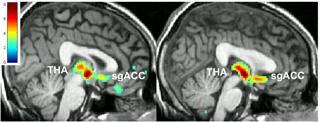

The team found that participants who reported improvement of depression symptoms after getting the placebo also had the strongest mu-opioid response in brain regions involved in emotion and depression. And these individuals were also more likely to experience even fewer symptoms once they got a real drug.

The new findings were made using position emission tomography, or PET, scanning, and a substance that attaches to the receptors on brain cells that mu-opioid molecules bind to. In the single-blind randomized crossover design, the participants went in knowing that they wouldn't be told full details about the purpose of the study until the end.

They then received two weeks of placebo pill treatment - but during one of those weeks, each was told they were taking a substance that is believed to activate internal mechanisms and may have antidepressant properties. At the end of this week, they also came for a brain scan and received an injection of harmless salt water that they were told might have fast-acting antidepressant properties. After these two weeks and scan, they were prescribed a real antidepressant. They reported their depression symptoms using standard measurement scales throughout the study period.